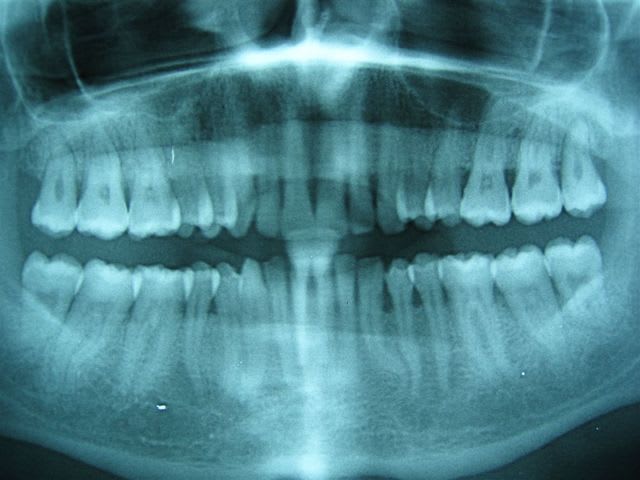

24/03/2007 à 11h32

... il a 27 ans.

U - Eugenol

... on fait ça à plusieurs: ortho, stomato, implanto peut-être.

Le gosse a l'air motivé.

la chevauchée fantastique!